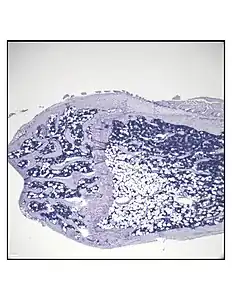

Representative distal femur histologic section of a 16-week-old C57BL/6 mouse after 6 weeks of calorie restriction demonstrating an increased quantity of marrow adipocytes.